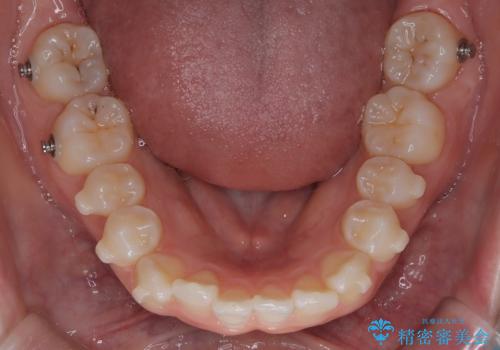

- 前歯のデコボコ(叢生)を気にされてご来院されました。精密な検査の結果、歯が並ぶスペースが不足していることが判明。患者様のご希望から、透明で目立ちにくいインビザライン(マウスピース矯正)による治療計画を立案しました。抜歯を避け、奥歯全体を奥へ動かす遠心移動という方法でスペースを確保し、前歯の叢生を解消することを目指します。

今回の矯正治療では、透明なマウスピース型の装置インビザラインを使用しました。この装置は取り外し可能で、日常生活で目立ちません。治療は、緻密に計算された計画に基づき、段階的に作製されたマウスピースを交換していくことで、奥歯から順に全体を後方へ移動させる遠心移動を実施。これにより、前歯を並べるための十分なスペースが確保され、デコボコが解消されました。抜歯することなく、機能的にも審美的にも整った美しい歯並びを獲得していただけました。